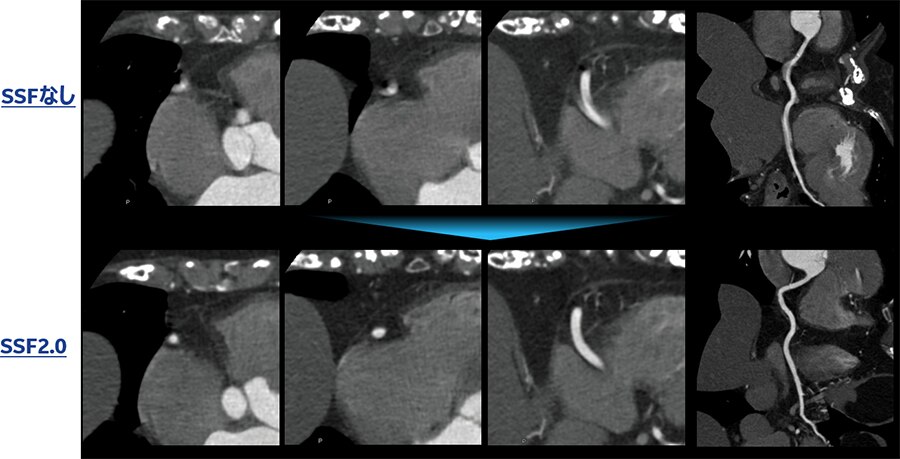

Fig.7 SSFなし、SSF、SSF2.0比較例